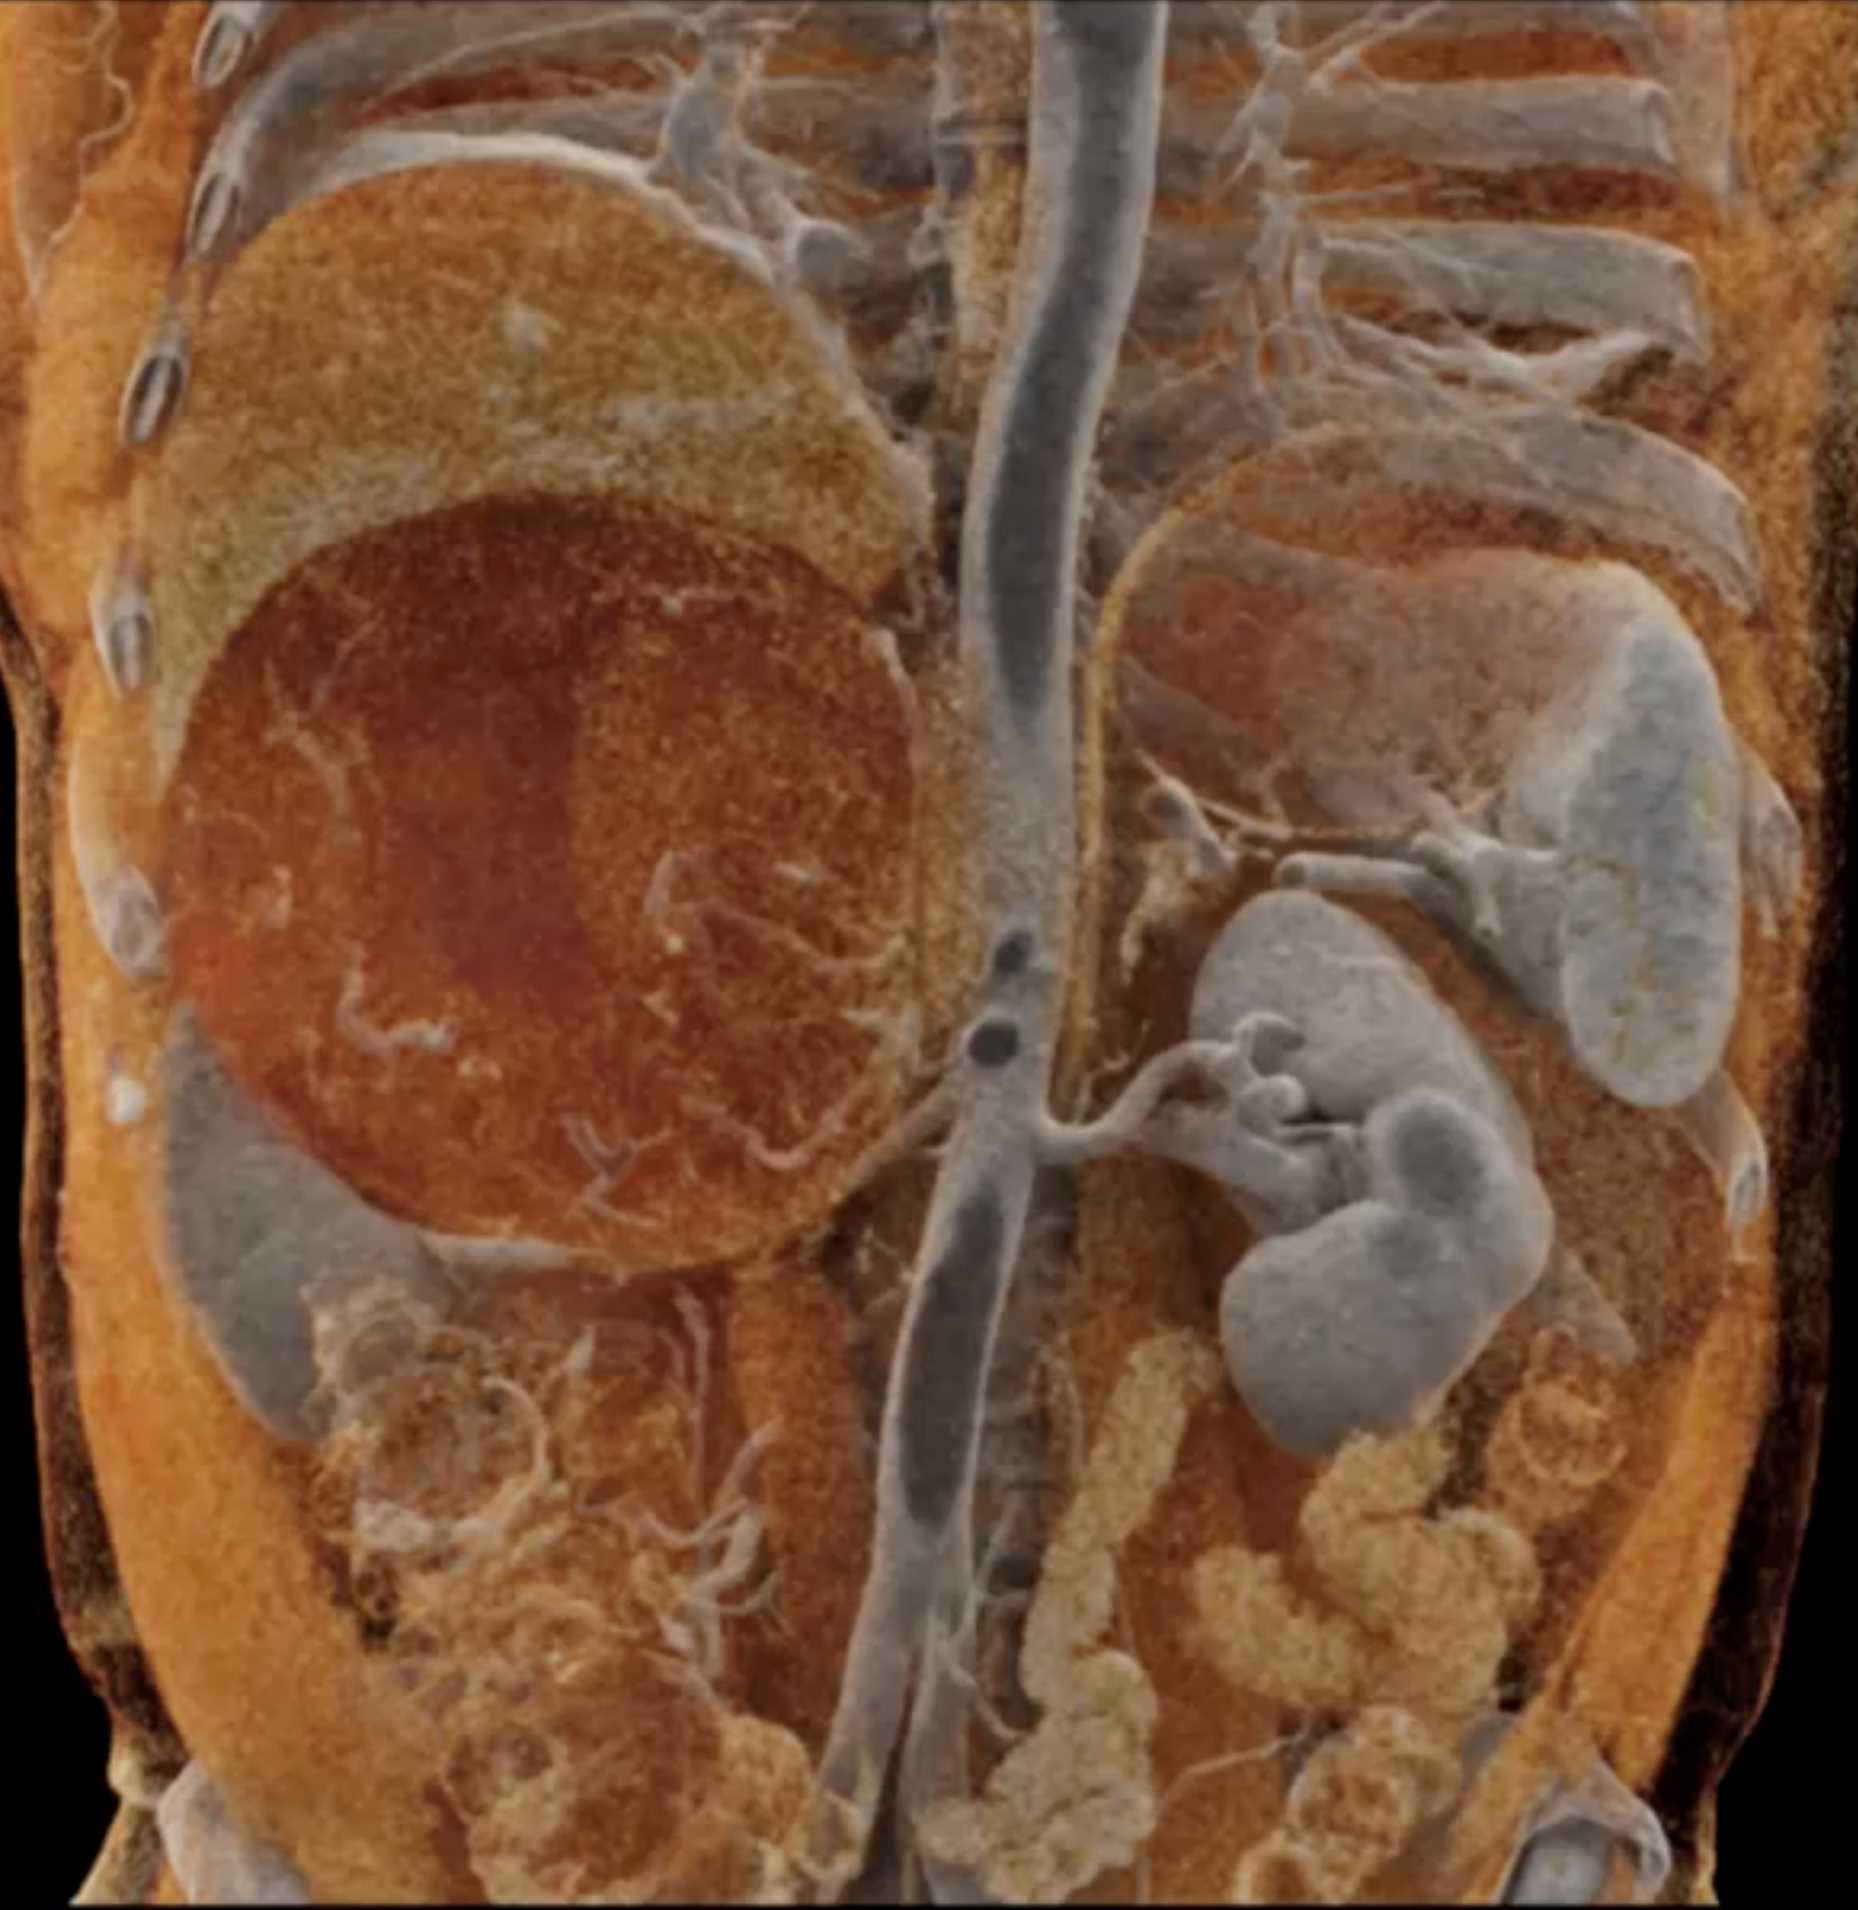

Left Adrenal Metastases from Renal Cell Carcinoma